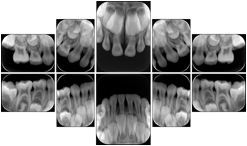

3. A dental provider wishes to capture a series of DICOM IO images for the patient’s dentition. The tooth morphology, teeth are divided into molars, premolars, canines and incisors, and a number of images for each jaw. The anatomic information was captured utilizing the triplet of schema. This standard code sequence is based on ISO 3950-2010, Dentistry - Designation system for teeth and areas of the oral cavity.

Every IO image should have anatomic information either through the primary or modifier sequence.

In most standard cases, images are oriented in structured layouts. These structured displays are useful to be shared between providers for reference purposes.

Table OO.1.1-1 shows structured display standard templates, where Viewset ID is based on the Japanese Society for Oral and Maxillofacial Radiology (JSOMR) classification provided by JIRA (Japan Medical Imaging and Radiological Systems Industries Association, www.jira-net.or.jp). Expected or typical teeth to be imaged location, region and designation codes are based on ISO 3950-2010, Dentistry - Designation system for teeth and areas of the oral cavity. For all the hanging protocols listed in OO.1.1-1, the value to use for Hanging Protocol Creator (0072,0008) is "JSOMR" and the value to use for Hanging Protocol Name (0072,0002) does not include "JSOMR" (e.g., "DL-S001A", not "JSOMR DL-S001A").